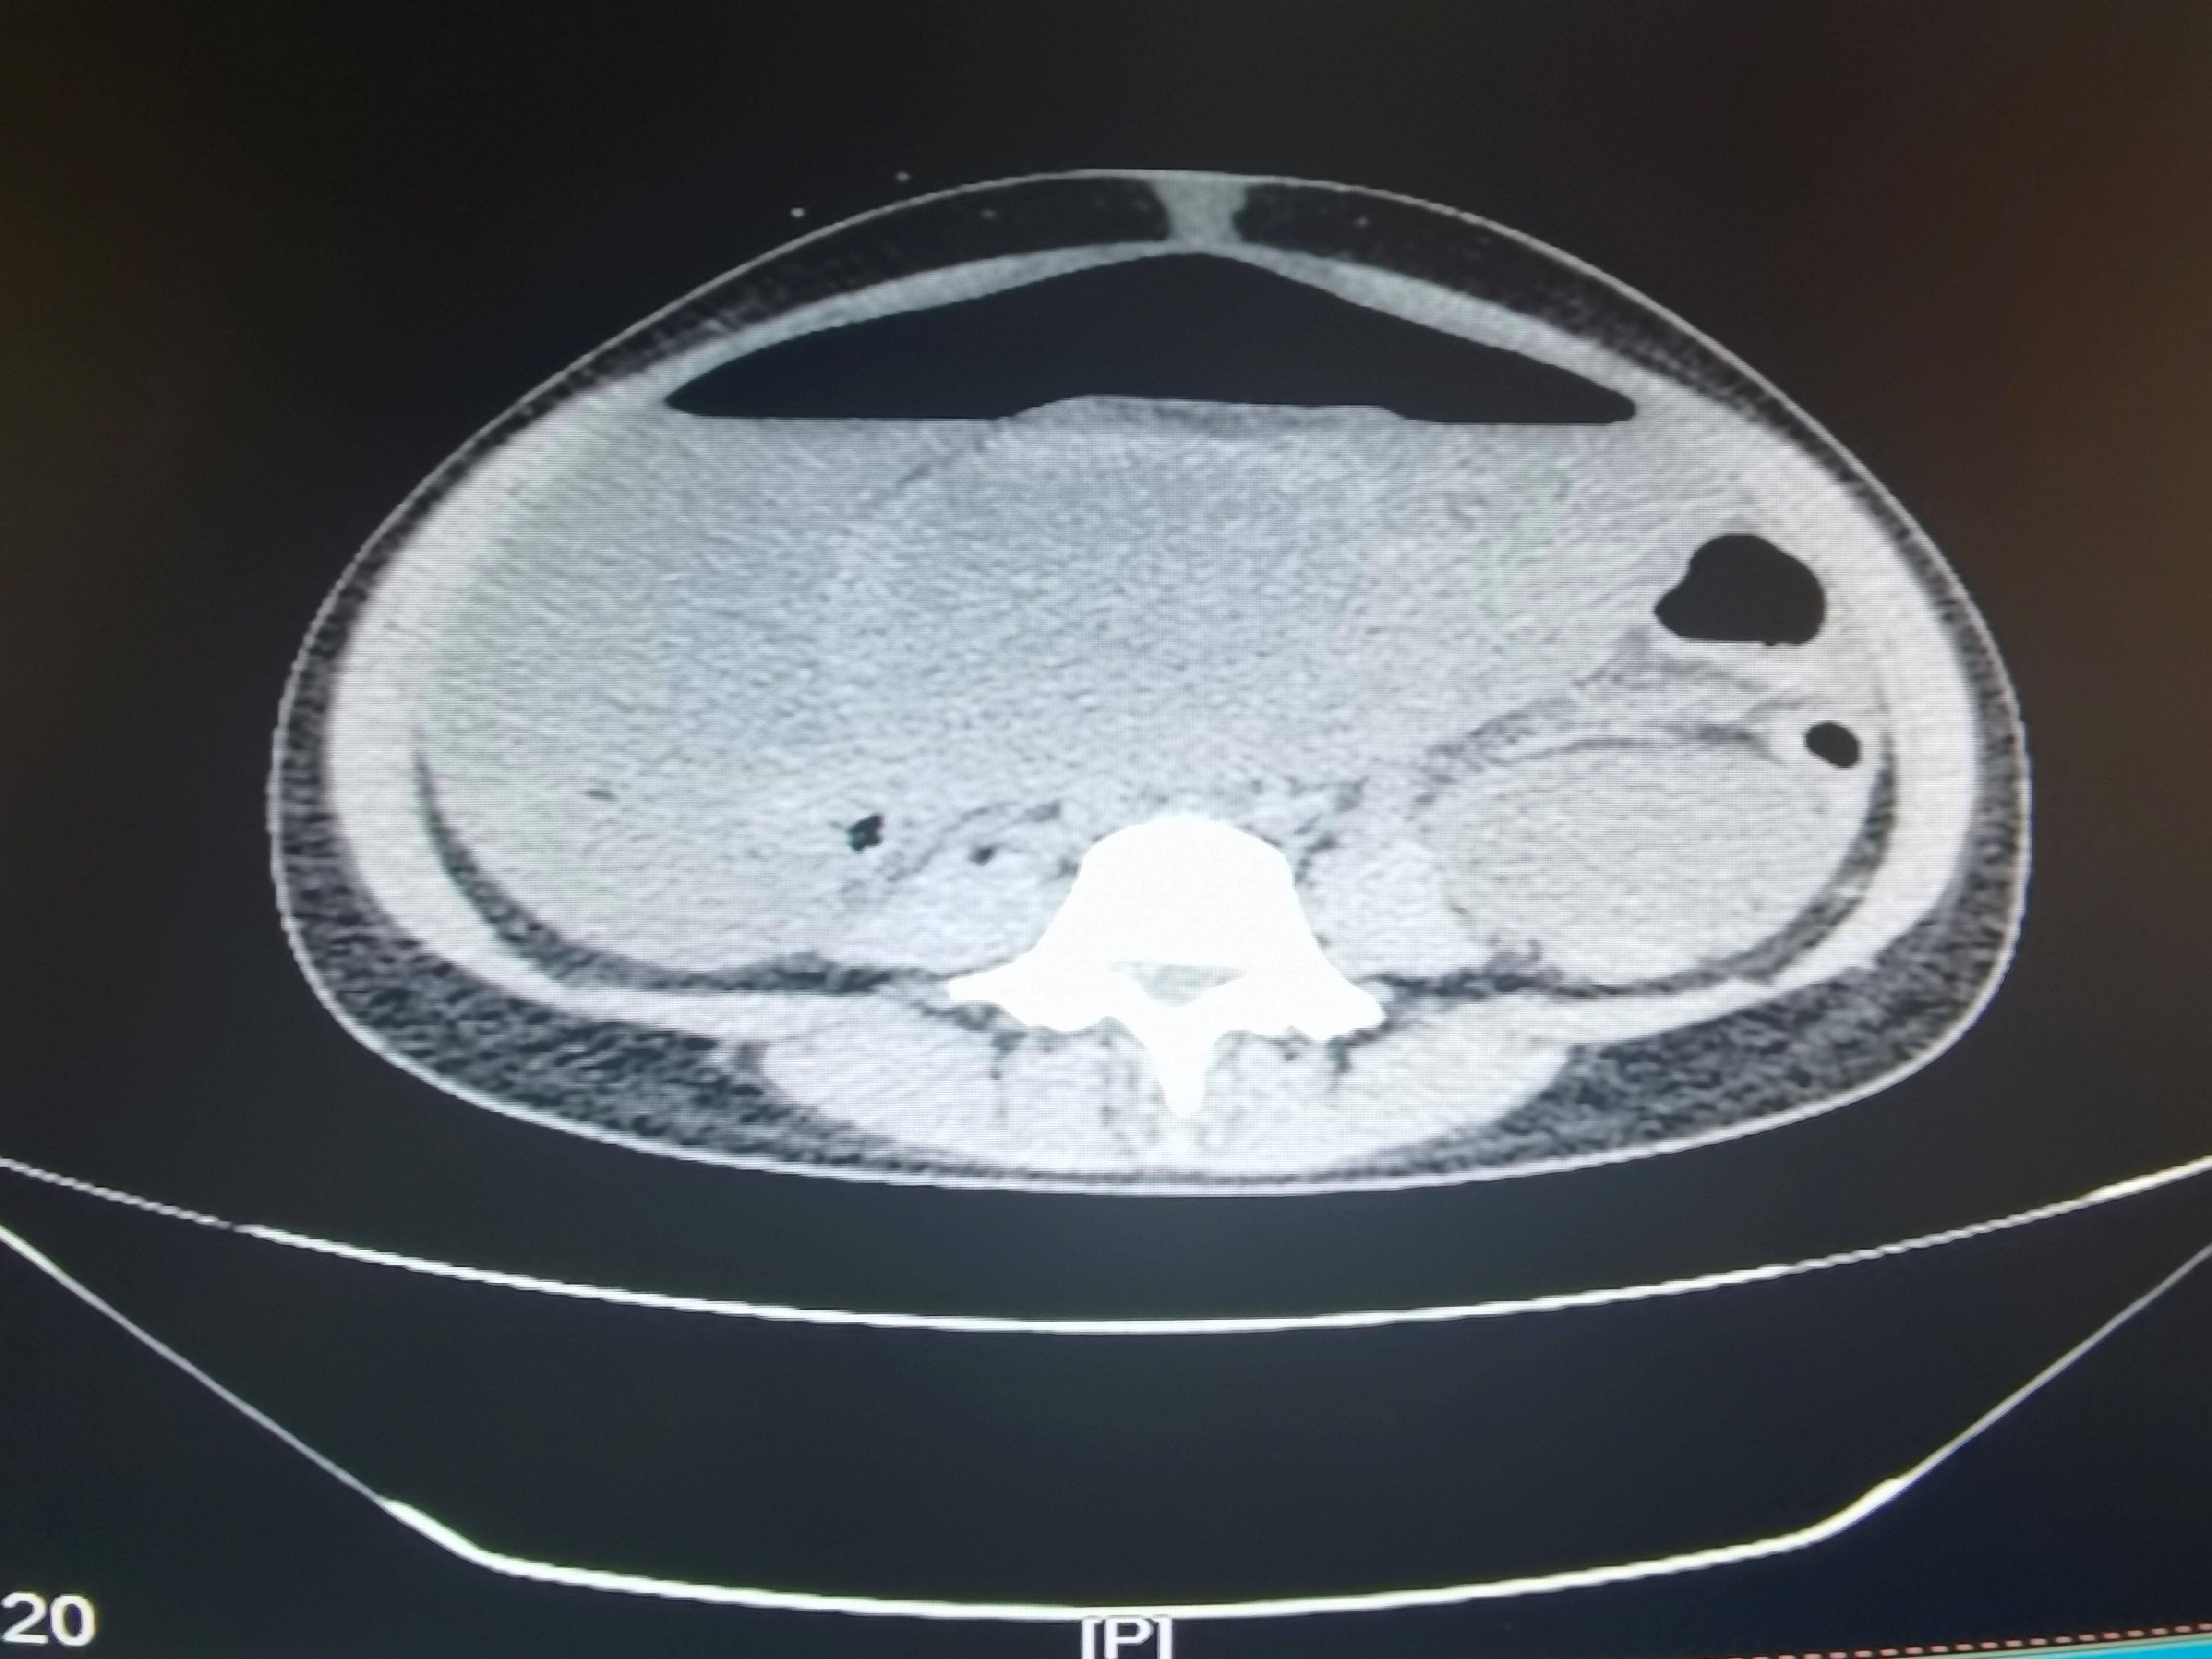

◈ 2021年7月8日,患者为求手术治疗就诊于我院门诊,行腹部CT检查提示:盆腔见不规则低密度影,包绕膀胱及子宫,与双侧附件及邻近肠管、右侧髂血管分界不清,三期CT值约为28Hu、27Hu、34Hu,其内密度不均,可见片状高密度影及钙化密度影。检查诊断:盆腔占位病变,考虑粘液瘤可能性大,建议进一步检查(因放射科无法获得胃肠间质瘤诊断及治疗病史)。结合患者病史及腹部CT结果,目前患者肿瘤包绕膀胱及子宫,与双侧附件分界不清。术中可能需要切除附件,因患者为年轻未婚未育女性,且直接手术的临床价值尚不明确,暂不考虑手术治疗。建议继续给予口服伊马替尼400mg QD。

2021年7月8日 腹部CT